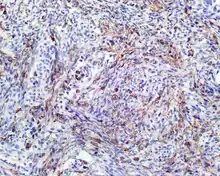

• S100 protein (a tumor marker protein) is focal, patchy to diffuse in all tumors.

S100 protein reaction in a biphenotypic sinonasal sarcoma

• Smooth-muscle actin or muscle-specific actin is seen in nearly all tumors, but a strong and diffuse reaction with SMA is seen in only about 50% of cases.

Smooth-muscle actin reaction in a biphenotypic sinonasal sarcoma

• No reactivity occurs with other tumor markers such as SOX10, myogenin, estrogen receptor, progesterone receptor, or keratins.